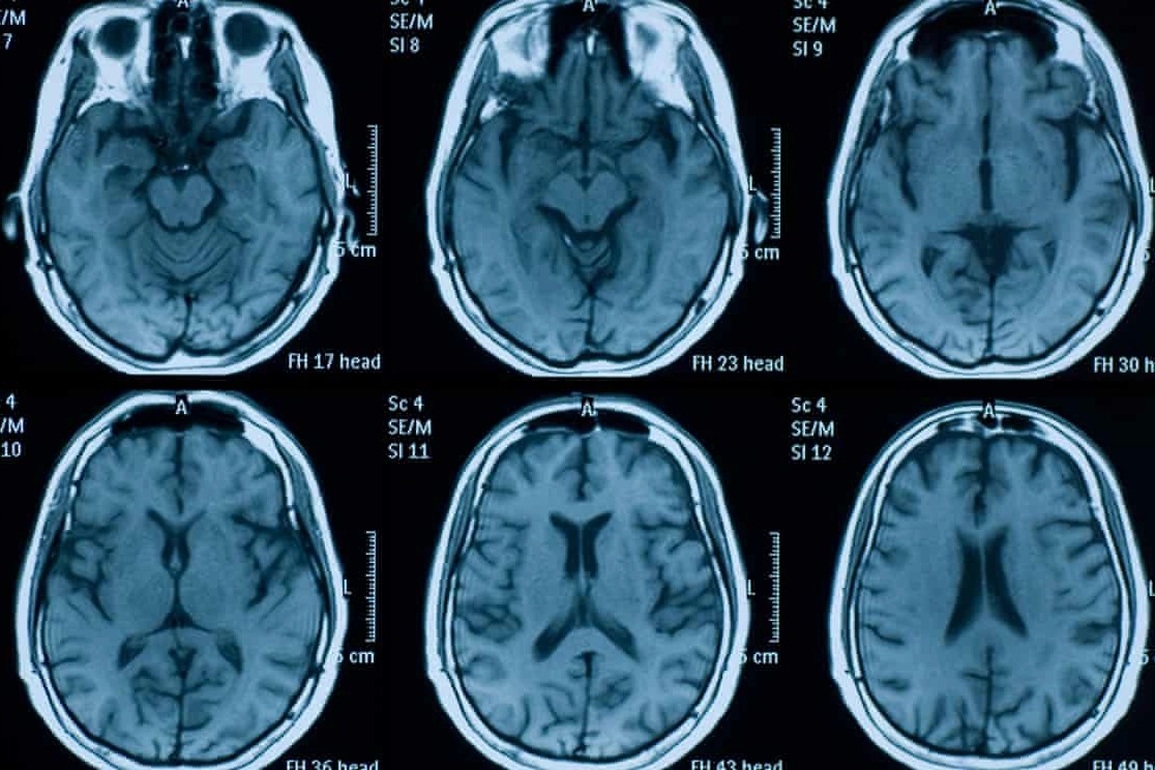

Nghiên cứu được công bố trên tạp chí Nature và cũng là công trình khoa học lớn đầu tiên so sánh các hình ảnh chụp não của bệnh nhân trước và sau khi mắc Covid-19 đã cho thấy sự co rút và tổn thương mô ở các vùng liên quan đến khả năng khứu giác và tinh thần vài tháng sau khi các bệnh nhân này có kết quả dương tính SARS-CoV-2.

So với 384 đối tượng tham gia nghiên cứu không bị nhiễm Covid-19, những người có kết quả xét nghiệm dương tính với SARS-CoV-2 có tổng thể não và chất xám bị teo lại nhiều hơn, đặc biệt là ở các khu vực liên quan đến khứu giác.

Cụ thể, theo kết quả nghiên cứu, những người bị Covid-19 mất thêm 1,8% hồi hải mã, vùng quan trọng của khứu giác trong não bộ và thêm 0,8% tiểu não, so với những người đối chứng.

Quá trình xử lý tín hiệu bị gián đoạn trong những khu vực như vậy có thể góp phần gây ra các triệu chứng như mất mùi. Những người bị nhiễm cũng thường đạt điểm thấp hơn trong bài kiểm tra khả năng tư duy so với những người không bị nhiễm. Điểm số thấp hơn có liên quan đến sự mất mát nhiều hơn của mô não trong các phần của tiểu não liên quan đến khả năng tư duy.